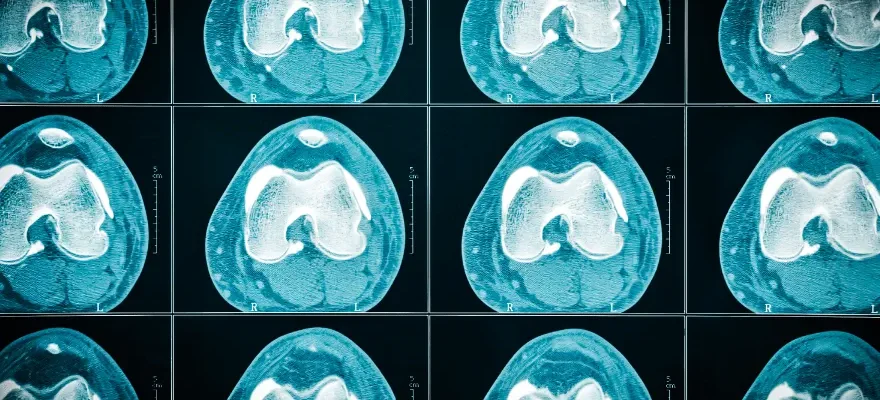

Diz BT, diz eklemini ve çevresindeki yumuşak dokuları, kemikleri ve diğer yapıları detaylı bir şekilde incelemek için kullanılan bir bilgisayarlı tomografi taramasıdır. Bu tarama, kesit kesit görüntüler elde ederek, dizin iç yapısını üç boyutlu olarak gösterir. Diz BT, özellikle kemik yapıları ve eklem içi detaylar üzerinde yüksek çözünürlüklü görüntüler sağlar, bu da ortopedistlerin ve diğer sağlık profesyonellerinin hastalıkların tanısını koymasında ve tedavi planlamasında önemli bir rol oynar.

Diz BT çekimi sırasında, hasta genellikle sırtüstü yatar ve ilgili bacak tarama cihazının içine yerleştirilir. Bacağın hareketsiz kalması gerektiği için, çoğu zaman bacak sabitleyici cihazlar kullanılır. Tarama, genellikle birkaç dakika içinde tamamlanır. Eğer detaylı bir inceleme gerekiyorsa, kontrast madde kullanılarak yapılan çekimler de söz konusu olabilir. Bu durumda, kontrast madde damar yoluyla verilir ve dizin çevresindeki damar ve yumuşak dokuların daha net görüntülenmesi sağlanır. Tarama sonrasında elde edilen görüntüler, radyologlar tarafından incelenir ve bulgular bir rapor halinde doktora sunulur.